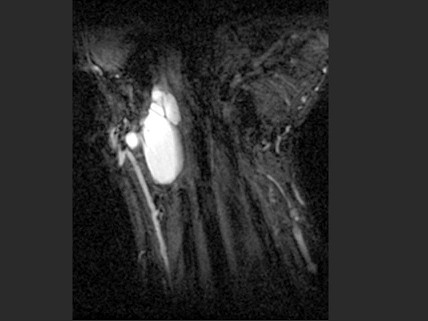

男,60岁,发现腕部肿块3个月,结合图像,最可能的诊断是()

A.舟状骨骨囊肿

B.腕部腱鞘囊肿

C.肌内脓肿

D.血管瘤

E.以上都不是